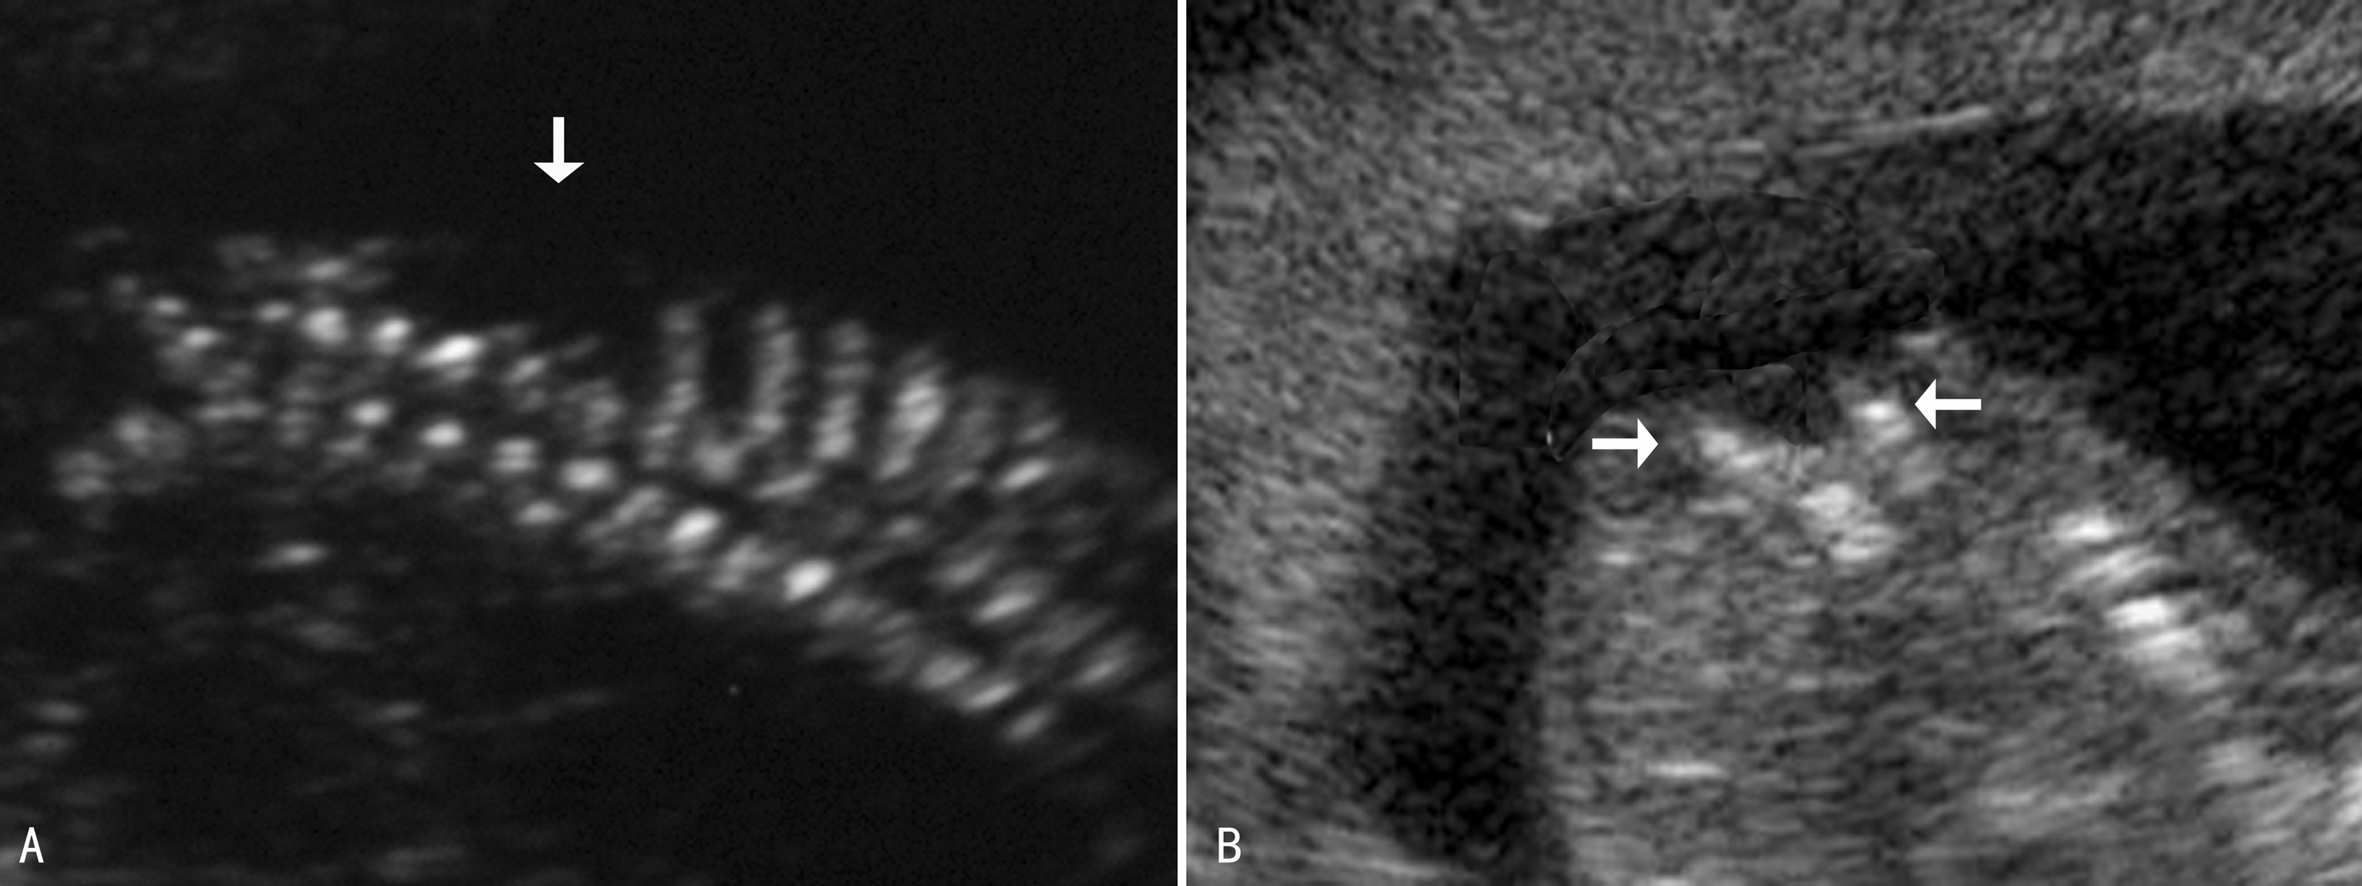

1. OSD 脊柱裂部位表面的皮肤和软组织回声连续性中断是OSD的直接超声征象。前侧的脊柱椎体强回声带存在,后侧强回声带消失;冠状面扫查显示椎管增宽,横断面显示正常三角形的脊柱骨化中心中后两个骨化中心消失或分离、增宽,呈典型的“U”形或者“V”形改变,羊水无回声区直接接触椎管或椎管软组织(图1)。

图1 OSD矢状面(A)及横断面(B)声像图(箭头)